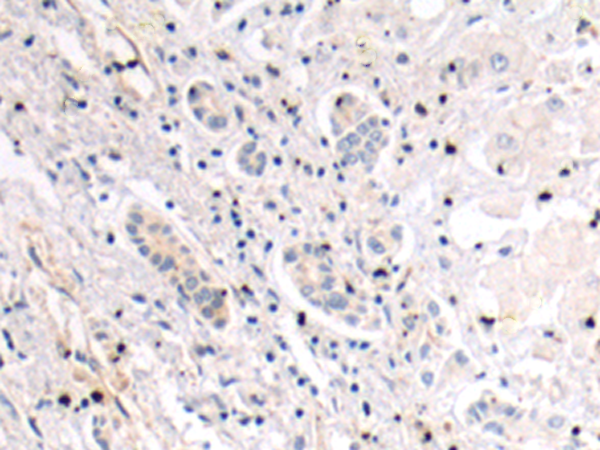

分类: 科研抗体货号: P10645别名: AM2; dJ579N16.4应用: IHC反应种属: Human, Mouse, Rat